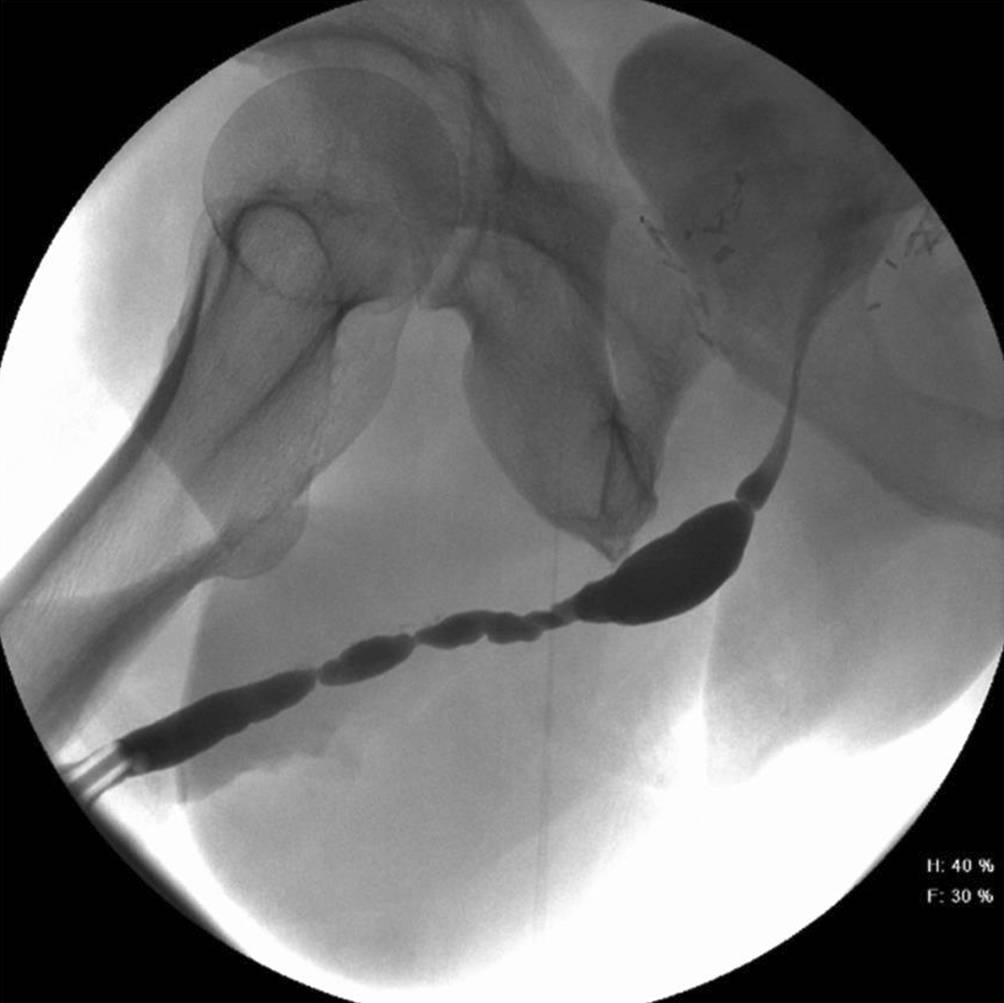

Penile und panurethrale Strikturen stellen ein komplexes und herausforderndes Krankheitsbild dar, wobei zur erfolgreichen Therapie oftmals mehrere Eingriffe notwendig werden. Dennoch sollte ein einzeitiges Verfahren mit Verwendung von Mundschleimhaut als Graft, wenn immer möglich, den ein- bis mehrzeitigen Operationen mit Einsatz von Lappen vorgezogen werden. Erschwerend kommt jedoch hinzu, dass neben der Komplexität der Behandlung keine ausgeprägte Evidenz für die Operation von längerstreckigen, penilen oder panurethralen Strikturen vorliegt. Die meisten panurethralen Urethraverengungen sind iatrogen durch traumatische Katheterisierung und transurethrale Eingriffe versursacht oder sogar idiopathischer Natur. Die Begleiterkrankung des Lichen sclerosus und die postentzündliche Veränderungen der Harnröhre folgen als weitere Ursachen [29]. Urethritiden erlebten durch die präventiven Massnahmen vor sexuell übertragbaren Erkrankungen bereits Ende des 20. Jahrhunderts einen dramatischen Rückgang (Abb. 3). Die penile Harnröhrenstriktur findet ihren Ursprung in fast 30 % der Fälle als Komplikation einer früheren Hypospadieoperation [29]. Die folgenden Methoden können zur Behandlung eingesetzt werden:

Abb. 3

Beispiel einer langstreckigen, penilen und bulbären Harnröhrenstriktur eines 62-jährigen Patienten mit Zustand nach multiplen Eingriffen